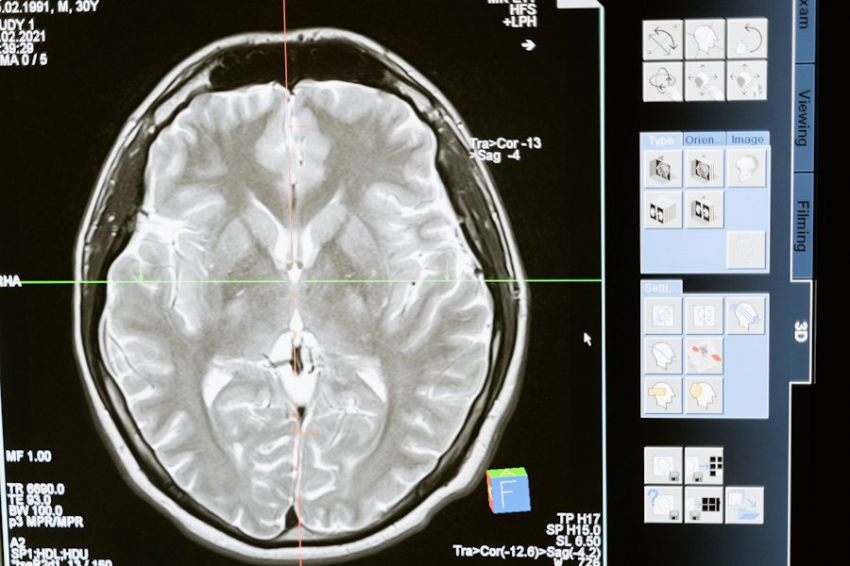

Профессор Джимо Борджигин из Мичиганского университета посвятила свое новое исследование на загадку того, что происходит в мозге человека в момент смерти. Об итогах уникального проекта рассказала Газета Балаково со ссылкой на материалы эксперимента.

В 2013 году Борджигин организовала опыт на крысах, показавший, что после остановки сердца у грызунов явно отмечалась повышенная активность мозга. А что с людьми? По традиционным представлениям, мозг после клинической смерти практически сразу отключается или работает на низком уровне.

В 2014 году команда Борджигин приступила к изучению активности мозга пациентов, умерших в отделении нейрореанимации. В частности, 24-летней беременной женщины, отключённой от аппарата жизнеобеспечения после глубокой комы. Как только ей удалили дыхательную трубку, мозг пациентки максимально усилил активность, особенно в тех областях, что ранее практически «безмолвствовали».

Были зафиксированы высокочастотные гамма-волны, обычно связанные со сновидениями и воспоминаниями. Они наблюдались более шести минут, пик активности длился около двух минут после отключения кислорода. Мозг пациентки был гиперактивен, – пояснила Борджигин.

При этом зоны мозга, отвечающие за сознание, демонстрировали мощную синхронизацию волн и активацию областей, связанных с эмпатией. Профессор пришла к выводу, что у пациентки был околосмертный опыт с такими его классическими признаками, как видение яркого света или вспоминание значимых моментов жизни.